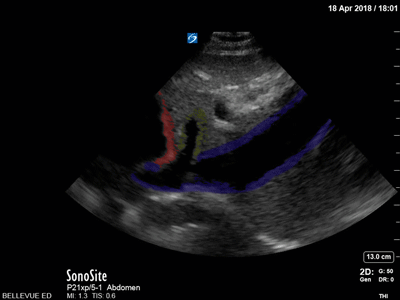

Inferior Vena Cava and Hepatic Vein Red: Heart, Yelow: Hepatic vein, Blue: Inferior vena cava Images: Dr. Lindsay Davis, Dr. Hannah Kopinski. Image Editing: Michael Amador and Dr. Matthew Riscinti